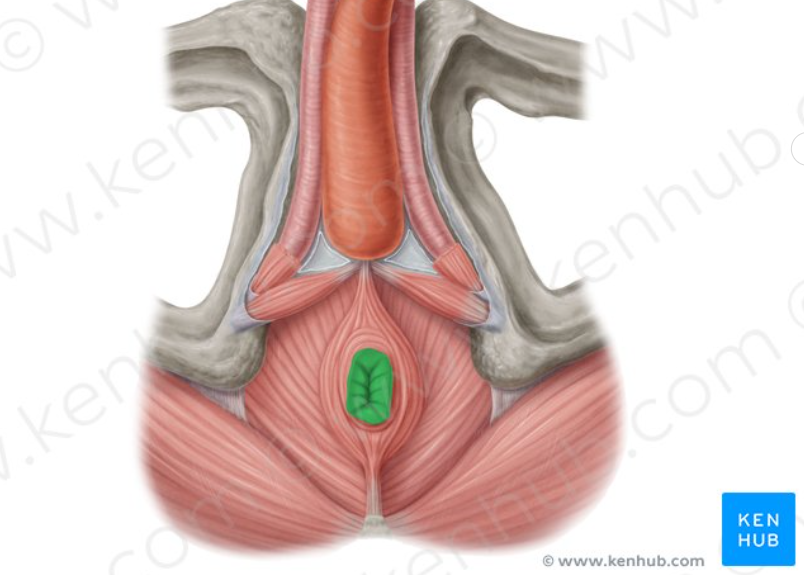

Rectum

the final section of the large intestine, terminating at the anus, that stores feces before elimination.

Anus

Internal Anal Sphincter

A thickened ring of smooth muscle that surrounds the anal canal. It is under involuntary control, meaning you don't consciously control its contraction or relaxation. It is normally contracted to maintain fecal continence.

Rectum

The final section of the large intestine, terminating at the anal canal. Its primary function is to store feces before they are eliminated from the body.

External Anal Sphincter

A ring of skeletal muscle that surrounds the anal canal, superficial to the internal anal sphincter. It is under voluntary control, meaning you can consciously choose to contract or relax it to control the passage of feces. This allows for the postponement of defecation.

Anus

The opening at the end of the digestive tract through which feces are eliminated from the body. It is surrounded by the internal and external anal sphincters, which regulate the passage of waste.